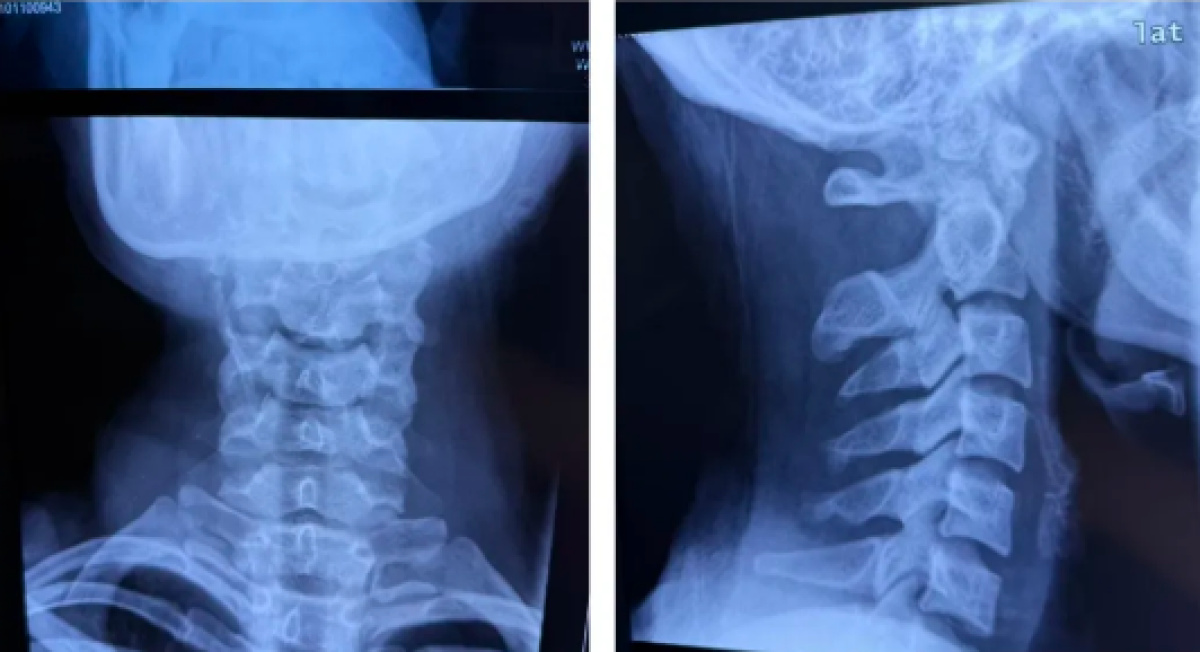

骨科主任张春雷团队接诊后,经过详细的查体及影像学检查发现,患者四肢麻木,双手握力4级,T4水平感觉减退,左手及腕部不能背伸,能动却不知道手在哪里——本体感觉和痛觉消失,确诊为“创伤性寰枢关节不稳伴不完全性瘫痪”。

这是一种严重的颈椎损伤,若不及时妥善处理,可能导致神经受压甚至瘫痪风险,严重影响未来生活。

手术历时2小时顺利完成,术中出血量控制良好。术后影像显示,其颈椎序列恢复理想,内固定位置精准。